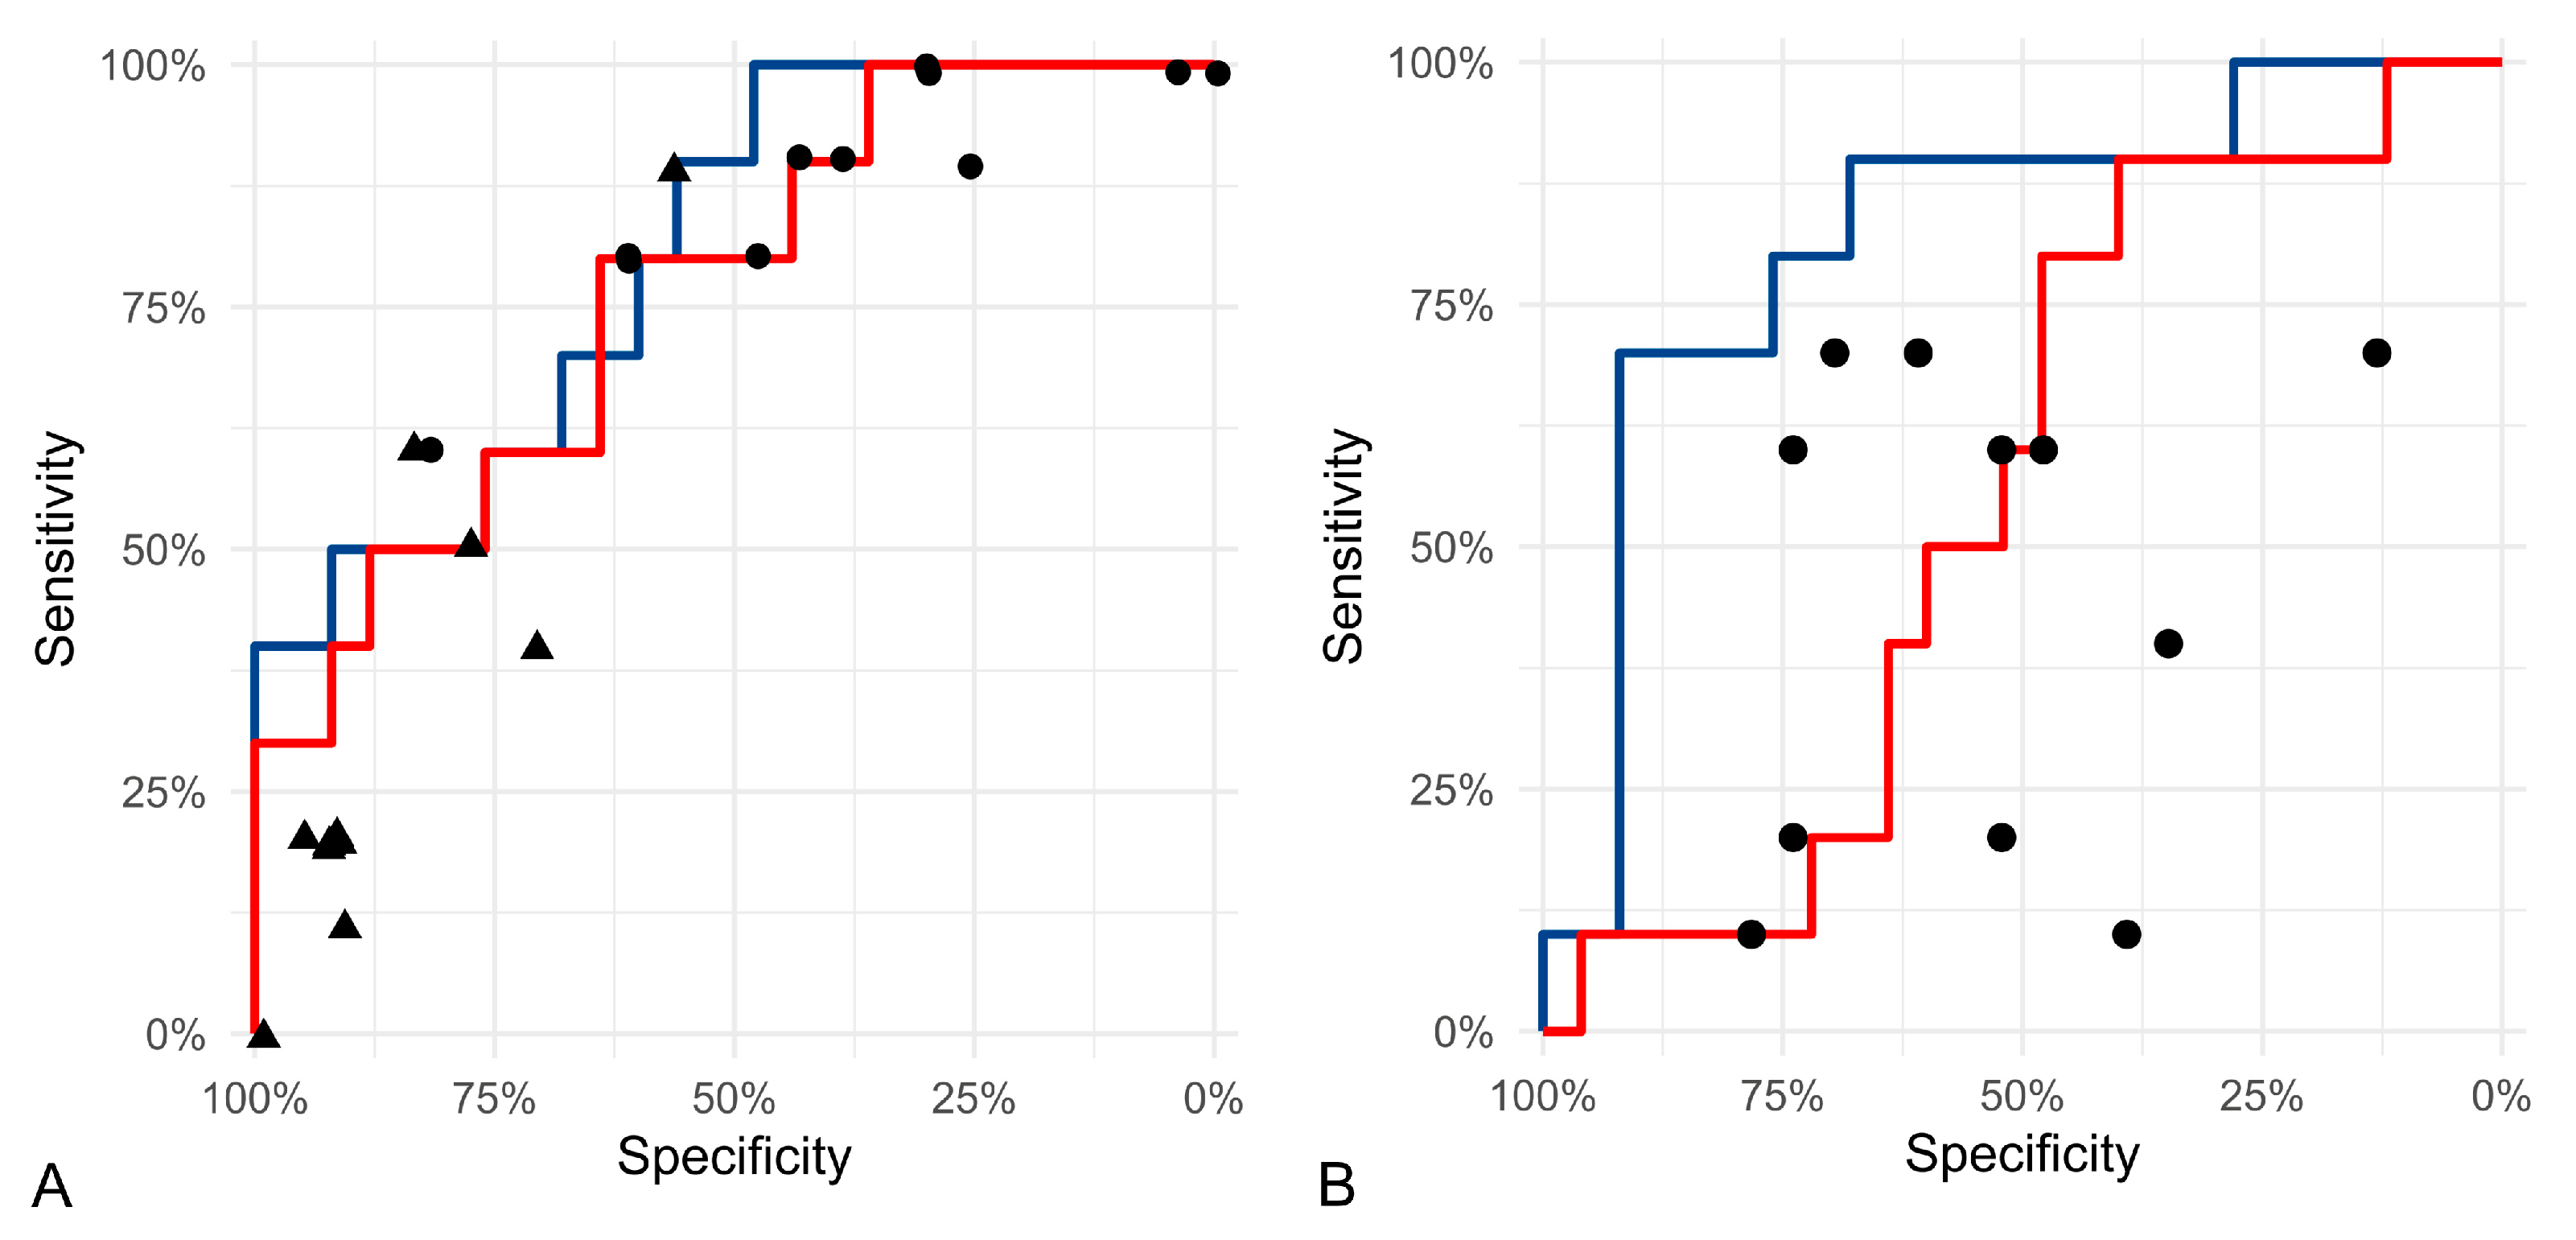

3.2. Test Accuracy of Algorithmic Morphometry

| Morphometric Parameter | Method | Threshold Value | Sensitivity | Specificity | Precision |

|---|---|---|---|---|---|

| SD of area | Algorithmic | 16 µm2 | 70.0% | 68.0% | 46.7% |

| Manual | 10 µm2 | 70.0% | 64.0% | 43.8% | |

| Mean area of largest 10% of the nuclei | Algorithmic | 70.5 µm2 | 70.0% | 72.0% | 50.0% |

| Manual | 53.03 µm2 | 70.0% | 64.0% | 43.8% | |

| 50 µm2 | 90.0% | 64.0% | 50.0% | ||

| Percentage of nuclei above 42.3 µm2 | Algorithmic | 19% | 70.0% | 68.0% | 46.7% |

| Manual | 26% | 70.0% | 76.0% | 53.8% | |

| SD of solidity | Algorithmic | 0.045 | 70.0% | 92.0% | 77.8% |

| Manual | 0.0204 | 70.0% | 48.0% | 35.0% |